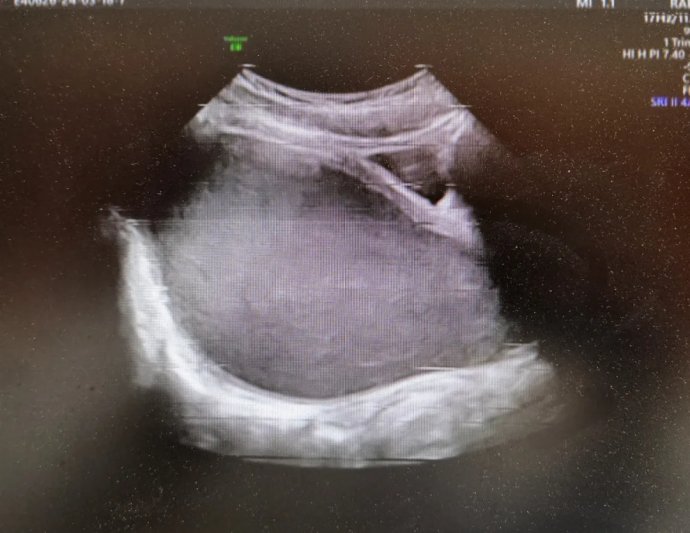

12岁花季少女出现周期性下腹痛,在其父母带领下先后就诊咸阳市两家医院,最终,她们选择了延安大学咸阳医院妇科。就诊当日,赵倩兰主管医生详细追问病史,患者自诉已间断性下腹痛3月余,本次腹痛较前明显加重,腹痛难忍。入院后医生立即为其安排了妇科彩超及盆腔磁共振,发现该患者宫腔、宫颈及阴道上段充满大量积血,积液压迫膀胱及直肠,导致排便、排尿障碍。张素宁主任为其查体后发现,该患儿阴道竟无开口,导致经血无法排出,闭锁处无隆起,无青紫,排除处女膜闭锁,直肠检查发现阴道上端有一包块凸向直肠,包块下缘距离肛门口约4-5cm,结合查体及相关辅助检查,考虑该患者为阴道闭锁,值得庆幸的是该患者其他系统暂未发现畸形。

妇科超声图